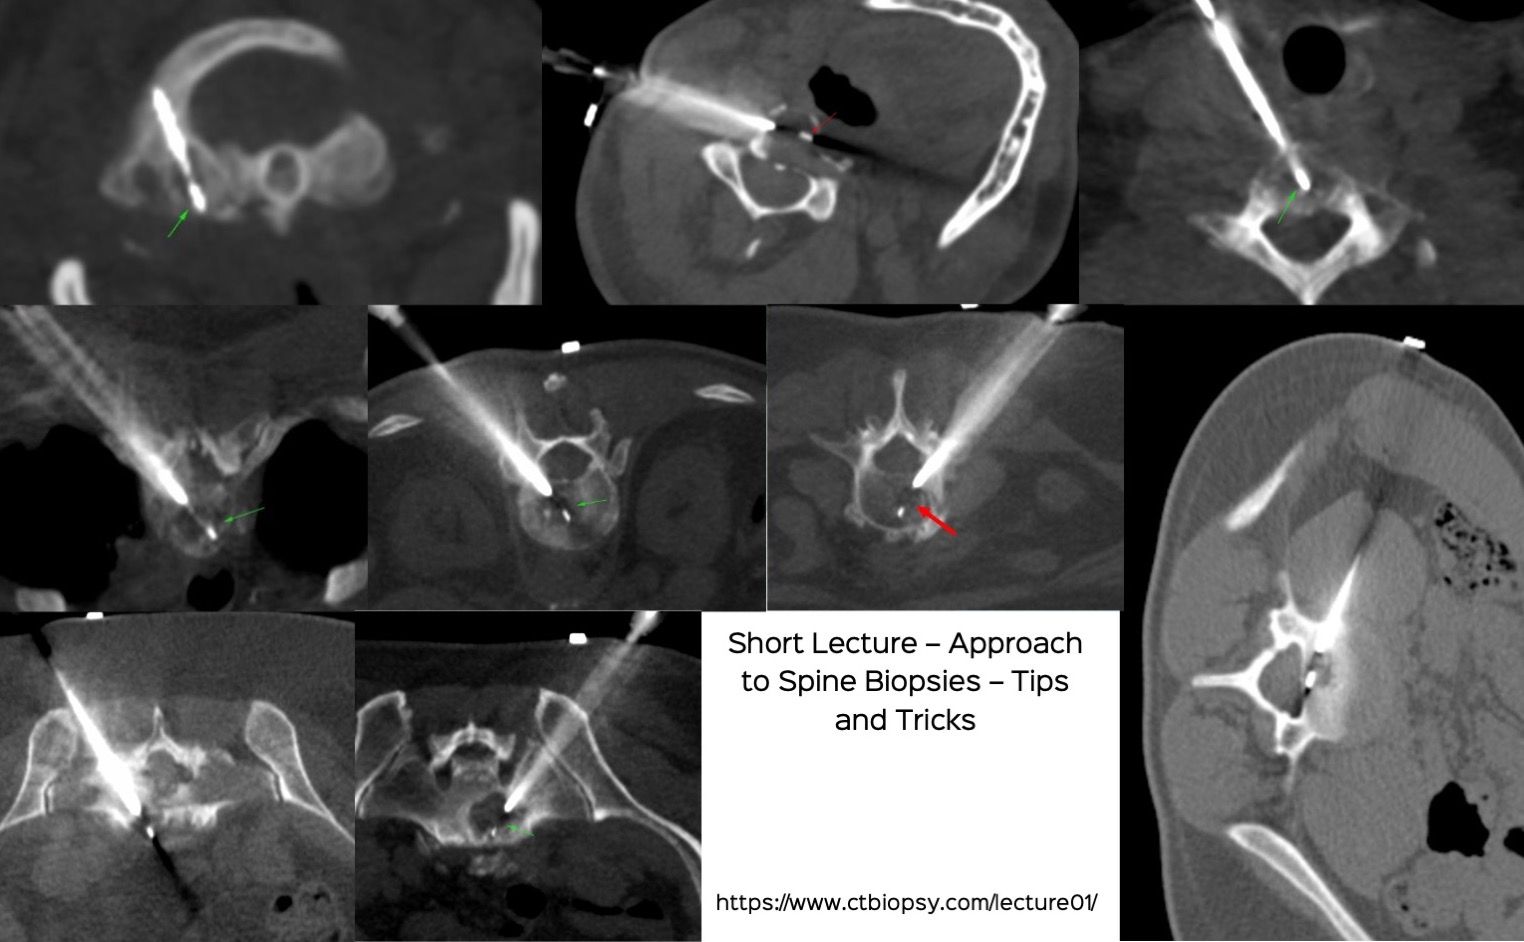

Lecture: Spine Biopsies - Tips and Tricks

Bhavin Jankharia - 12 December 2022